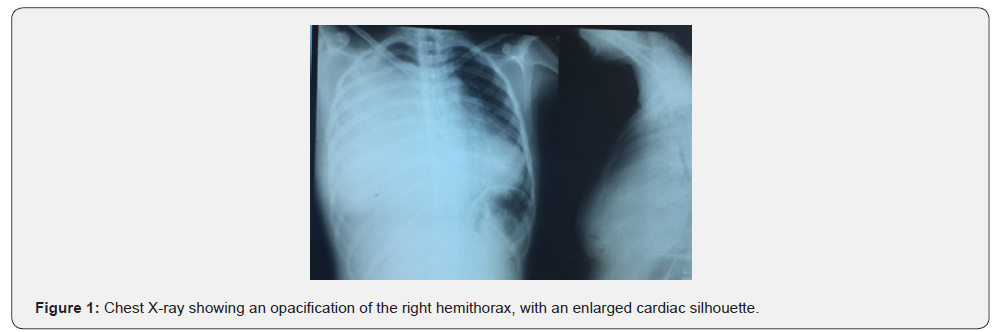

The electrocardiogram revealed a sinus tachycardia, a decreased electrocardiographic voltage without electrical alternans. The chest X-ray showed total opacification of the right hemithorax with an enlarged cardiac silhouette (Figure 1).